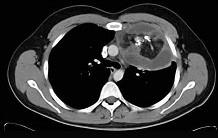

20岁,男,左胸痛伴压迫感,咳嗽1个月,请结合CT,检查选出最可能的诊断 ( )A.胸腺瘤B.纵隔血肿C.畸胎瘤D.脂肪瘤E.淋巴瘤

选项 A.胸腺瘤 B.纵隔血肿 C.畸胎瘤 D.脂肪瘤 E.淋巴瘤

答案 C